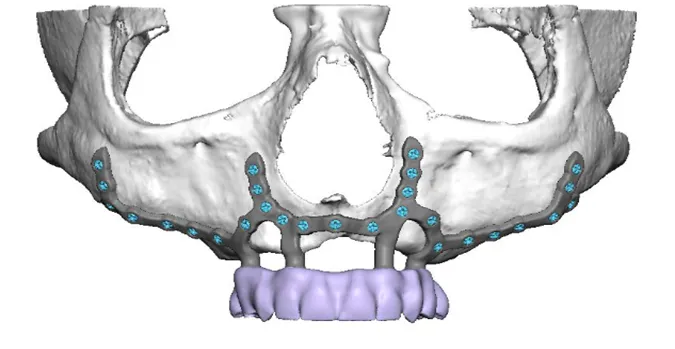

2. Digitales Design (CAD/CAM)

Auf Basis der 3D-Daten entsteht das virtuelle Implantat: Auflageflächen, Schraubenpositionen, Emergenzprofil – bereits prothetisch rückwärts geplant.

3. Chirurgische Platzierung (subperiostal)

Das PSI wird gewebeschonend auf dem Knochen positioniert und mit Mikroschrauben fixiert; Weichgewebe wird spannungsfrei verschlossen.